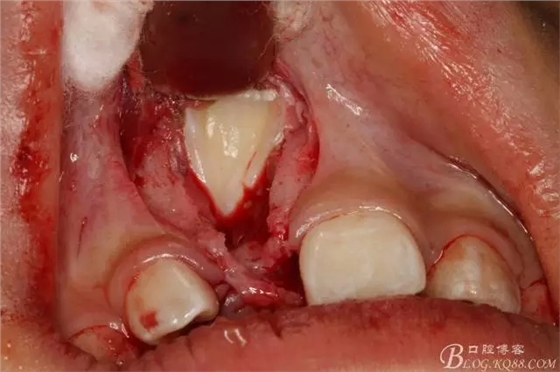

圖8.復(fù)位腭側(cè)水平瓣,行唇側(cè)梯形瓣,翻瓣、暴露隆起的骨面。

圖9.去骨、暴露11的舌面